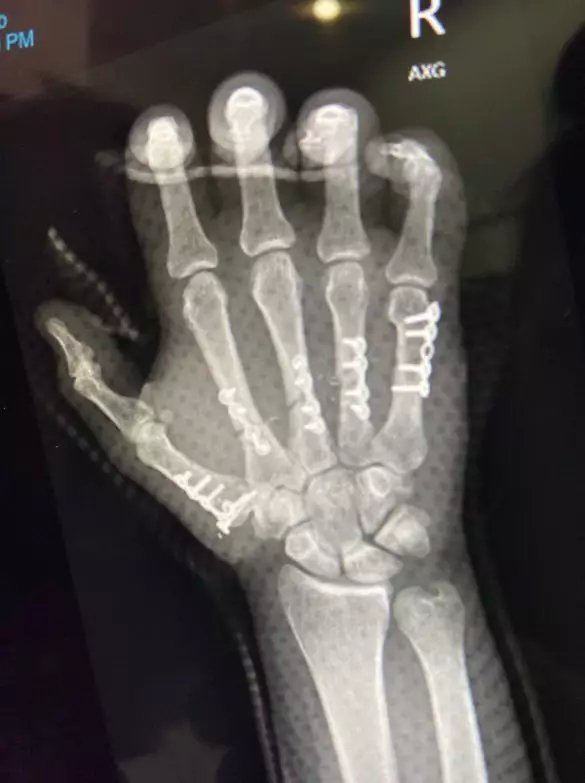

手术本身很困难,要完成关键动静脉和神经的重新连接,两位医生必须通过高倍显微镜完成毫米级别的目标,很多位置的缝合线太细,以至于肉眼很难辨别。

(图片来源:Brisbane Times)

最终,两位医生花费近8小时,完成了这次不可思议的手术。

(图片来源:Daily Mail)